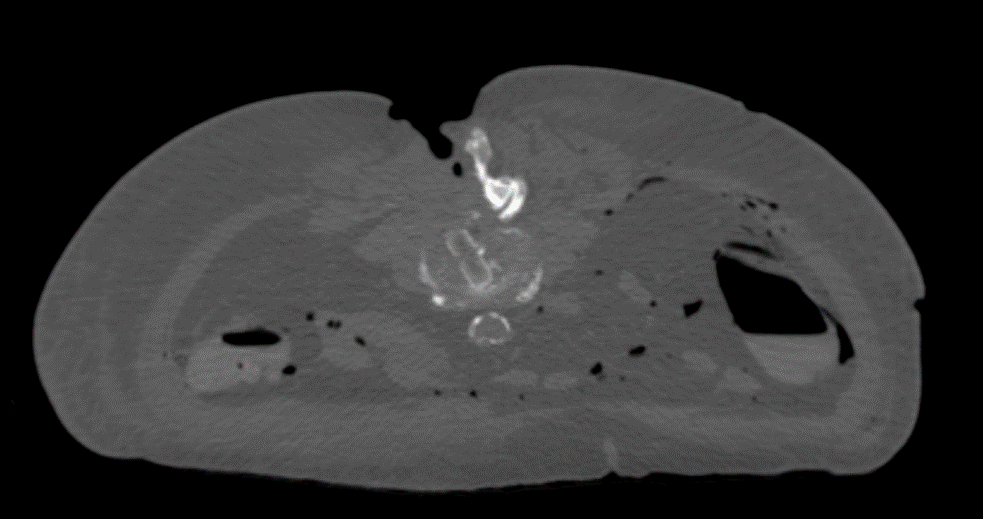

The PEEK core of the PROTI 360° cage has favorable imaging characteristics which support the postoperative assessment of fusion, while the titanium outer layer allows measurement of cage positioning. Clinically, depending on the image quality, plane of view, and patient anatomy, the PROTI 360° cage may show a ghost image of the entire cage on fluoroscopic images (Fig 7). CT images show minimal scatter around the implant (Fig 8).